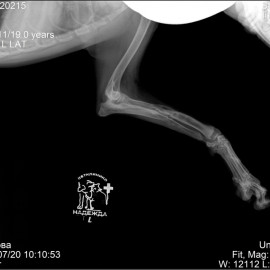

Собака по кличке Айза из города Ухта. Обратились в клинику с жалобами на сохраняющуюся хромоту на левую грудную конечность после полученных повреждений за 2 месяца до обращения к нам. После проведения осмотра и рентгенологического исследования было установлено: визуализируется костная мозоль в области средней трети диафиза левой лучевой и локтевой кости, левый локтевой сустава неконгруэнтный, деформаций локтевой кости по длине. Поставлен диагноз - анкилоз левого локтевого сустава, состояние после МОС левого предплечья, сросшийся перелом левой лучевой и локтевой кости. Была проведена операция - проксимальная динамическая остеотомия левой локтевой кости.

Снимок 3 после операции.